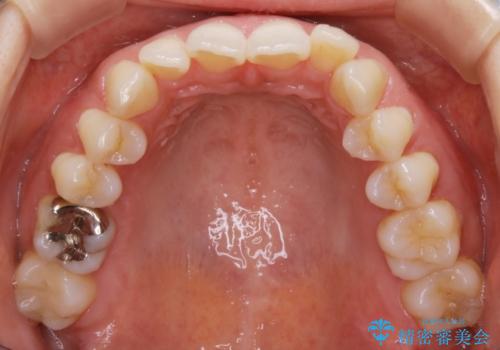

- 歯のガタつきによる見栄えや清掃困難を主訴にご来院されました。

左側の噛み合わせは上の歯が前方に寄ってきてしまっていることが原因のズレがありました。

ガタつき自体は歯列の幅の拡大やディスキング(IPR)でほとんど解消可能でしたが、噛み合わせのズレは歯の移動が必要だったため、左上にマイクロインプラントを使用し噛み合わせの改善とガタつきの解消を同時に進めるという方針をとりました。

歯列弓の拡大

歯並びが悪くなる原因の一つに「歯列弓の狭窄」というものがあります。

奥歯や前歯が内側(舌側)に倒れ込んでしまったり、歯が生えてくる位置が内側になってしまうことにより歯並びのアーチが狭くなってしまうことを言います。

このような場合、歯並びのアーチを拡大してあげるだけでもガタつきを無くすためのスペースがかなり作れることがあります。